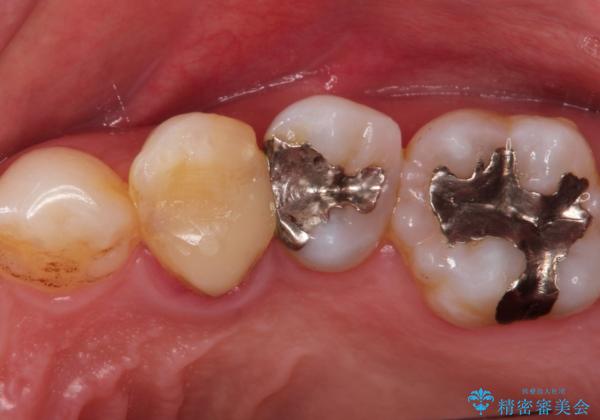

- 歯肉の下まで深く歯が折れたことを主訴に来院された患者様です。

かかりつけ医にて応急的に修復してますが根本的な治療を希望され、矯正的挺出を行ったのち、歯周外科を行い、歯冠修復をしております。